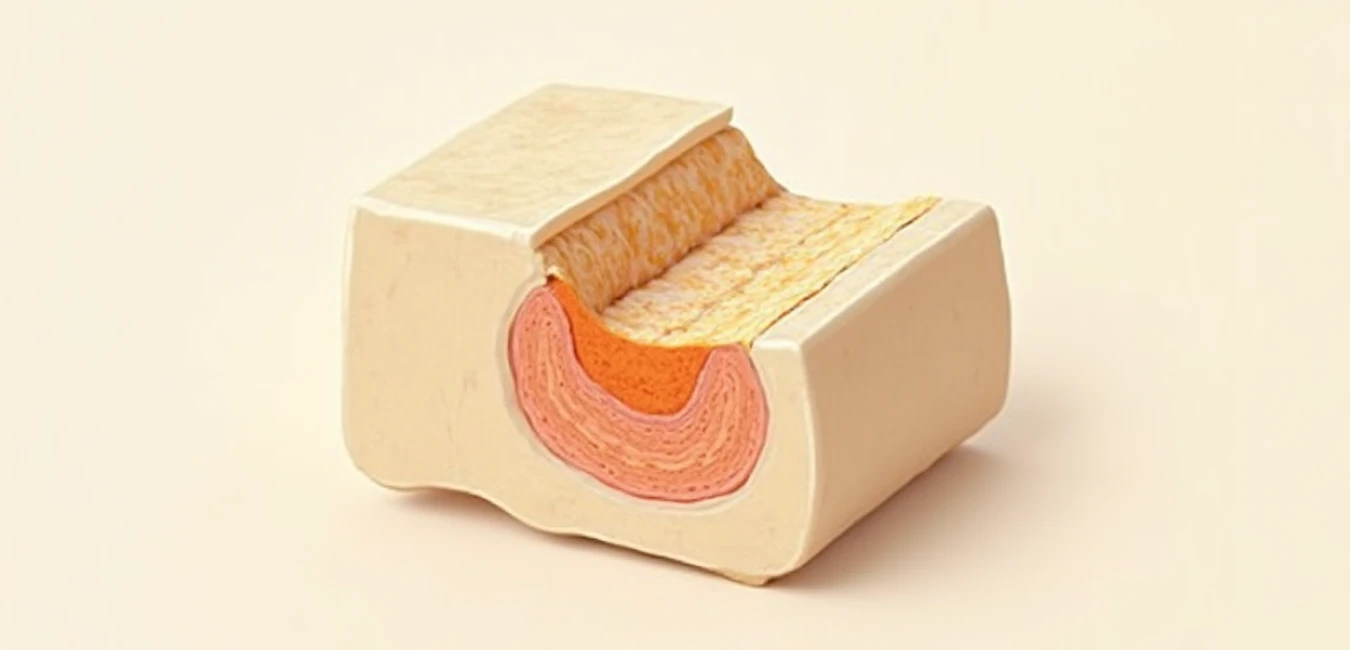

Stawy i kości stanowią kluczowe elementy układu ruchu człowieka. Kości tworzą szkielet wewnętrzny liczący około 206 elementów u dorosłego, dając wsparcie ciału i chroniąc narządy wewnętrzne. Stawy natomiast łączą te kości, zapewniając ruchomość i stabilność niezbędną do codziennej aktywności. Kość długa składa się z trzonu zbudowanego z tkanki kostnej zbitej, odpowiedzialnej za odporność mechaniczną, oraz nasad pokrytych tkanką gąbczastą, która zapewnia wytrzymałość przy niewielkiej masie. Od zewnątrz kość otacza okostna – błona zawierająca naczynia krwionośne i komórki kostne uczestniczące w regeneracji i wymianie składników kostnych co około 10 lat.

Chrząstka stawowa, pozbawiona unaczynnienia, czerpie składniki odżywcze z mazi stawowej, co czyni ją wrażliwą na zaburzenia krążenia tej płynnej substancji. Właściwa produkcja mazi i integralność chrząstki są kluczowe dla zachowania sprawności stawów. Kości natomiast wymieniają się dynamicznie – około 10% masy kostnej odnawia się rocznie u zdrowego dorosłego dzięki aktywności komórek w okostnej i wnętrzu kości. Ten proces regeneracji spowalnia z wiekiem, co zwiększa ryzyko osłabienia struktury kostnej.